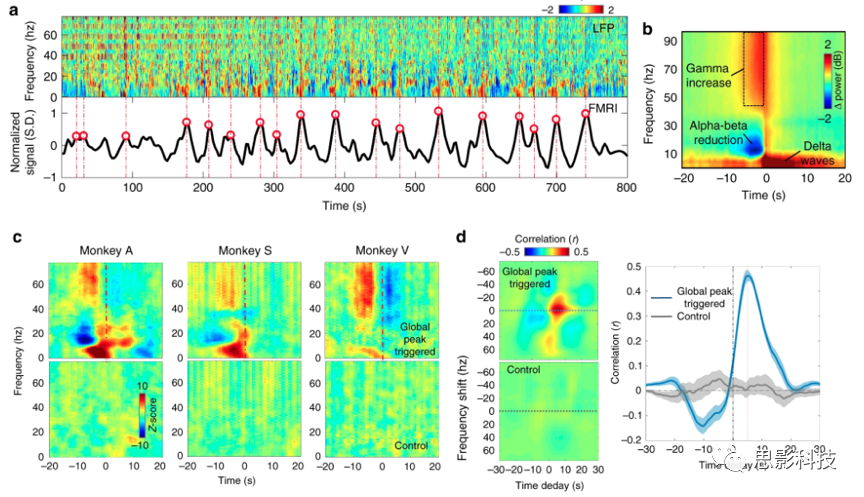

休息期间的皮层活动会被广泛的、同步的电生理和血流动力学信号打断,但它们的行为相关性尚不清楚。在这里,本研究发现这些事件其实对应于皮层兴奋的瞬间下降,并与基底前脑和丘脑的活动变化有关。结合猕猴的fMRI和电生理学,首先确定fMRI瞬变与局域场电位(LFPs)向低频的频谱转移同时发生。将这些知识应用于人类连接体项目的fMRI数据,结果发现fMRI瞬变在躯体感觉皮质最强。令人惊讶的是,正性皮层连接的瞬变与负性连接的瞬变同时发生在与觉醒调节有关的局灶性皮层下区域,最明显的是基底前脑。这种皮层下区域的参与,与LFP频谱转移的典型模式相结合,表明通常观察到的fMRI皮层活动的广泛变化与短暂的唤醒下降有关。

原文:Liu, X., de Zwart, J.A., Schölvinck, M.L. et al. Subcortical evidence for a contribution of arousal to fMRI studies of brain activity. Nat Commun 9, 395 (2018). https://doi.org/10.1038/s41467-017-02815-3